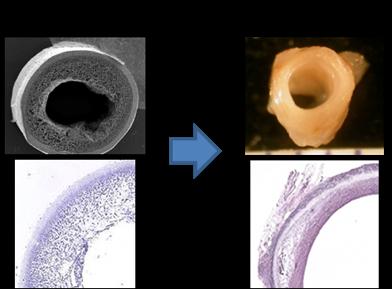

Research in Biomaterials

In the biomaterials area, Professor Kumta’s group focuses on the creation of clinically relevant novel biomaterials for next-generation therapies in regenerative medicine. His group is also currently developing novel materials for craniofacial and orthopedic applications comprising new biodegradable metals and injectable calcium phosphate (CaP)-based resorbable bone cements and polymers for mineralized tissue regeneration and stem cell viability. Additive manufacturing techniques are also employed to generate user specific scaffolds using biocompatible and biodegradable metals and ceramics. Research is also on-going to understand the effects of morphology, and surface structures of CaP based nanoparticles for targeted and surface mediated non-viral gene delivery. Biodegradable stents and drug eluting coatings are also under development to prevent coronary and pediatric pulmonary arterial sclerosis, repair intracranial aneurysms, and fill atrial septal defects. Another area of biocompatible materials under development is the understanding of cell-surface interaction between organic and inorganic materials as well as generation of chemical and biosensors for detection of biomarkers for cardiovascular and traumatic brain injury related conditions. His laboratories house a wide range of state-of-the-art equipment for materials synthesis and characterization, cell and tissue culture, and 3D printing of advanced materials and structures.